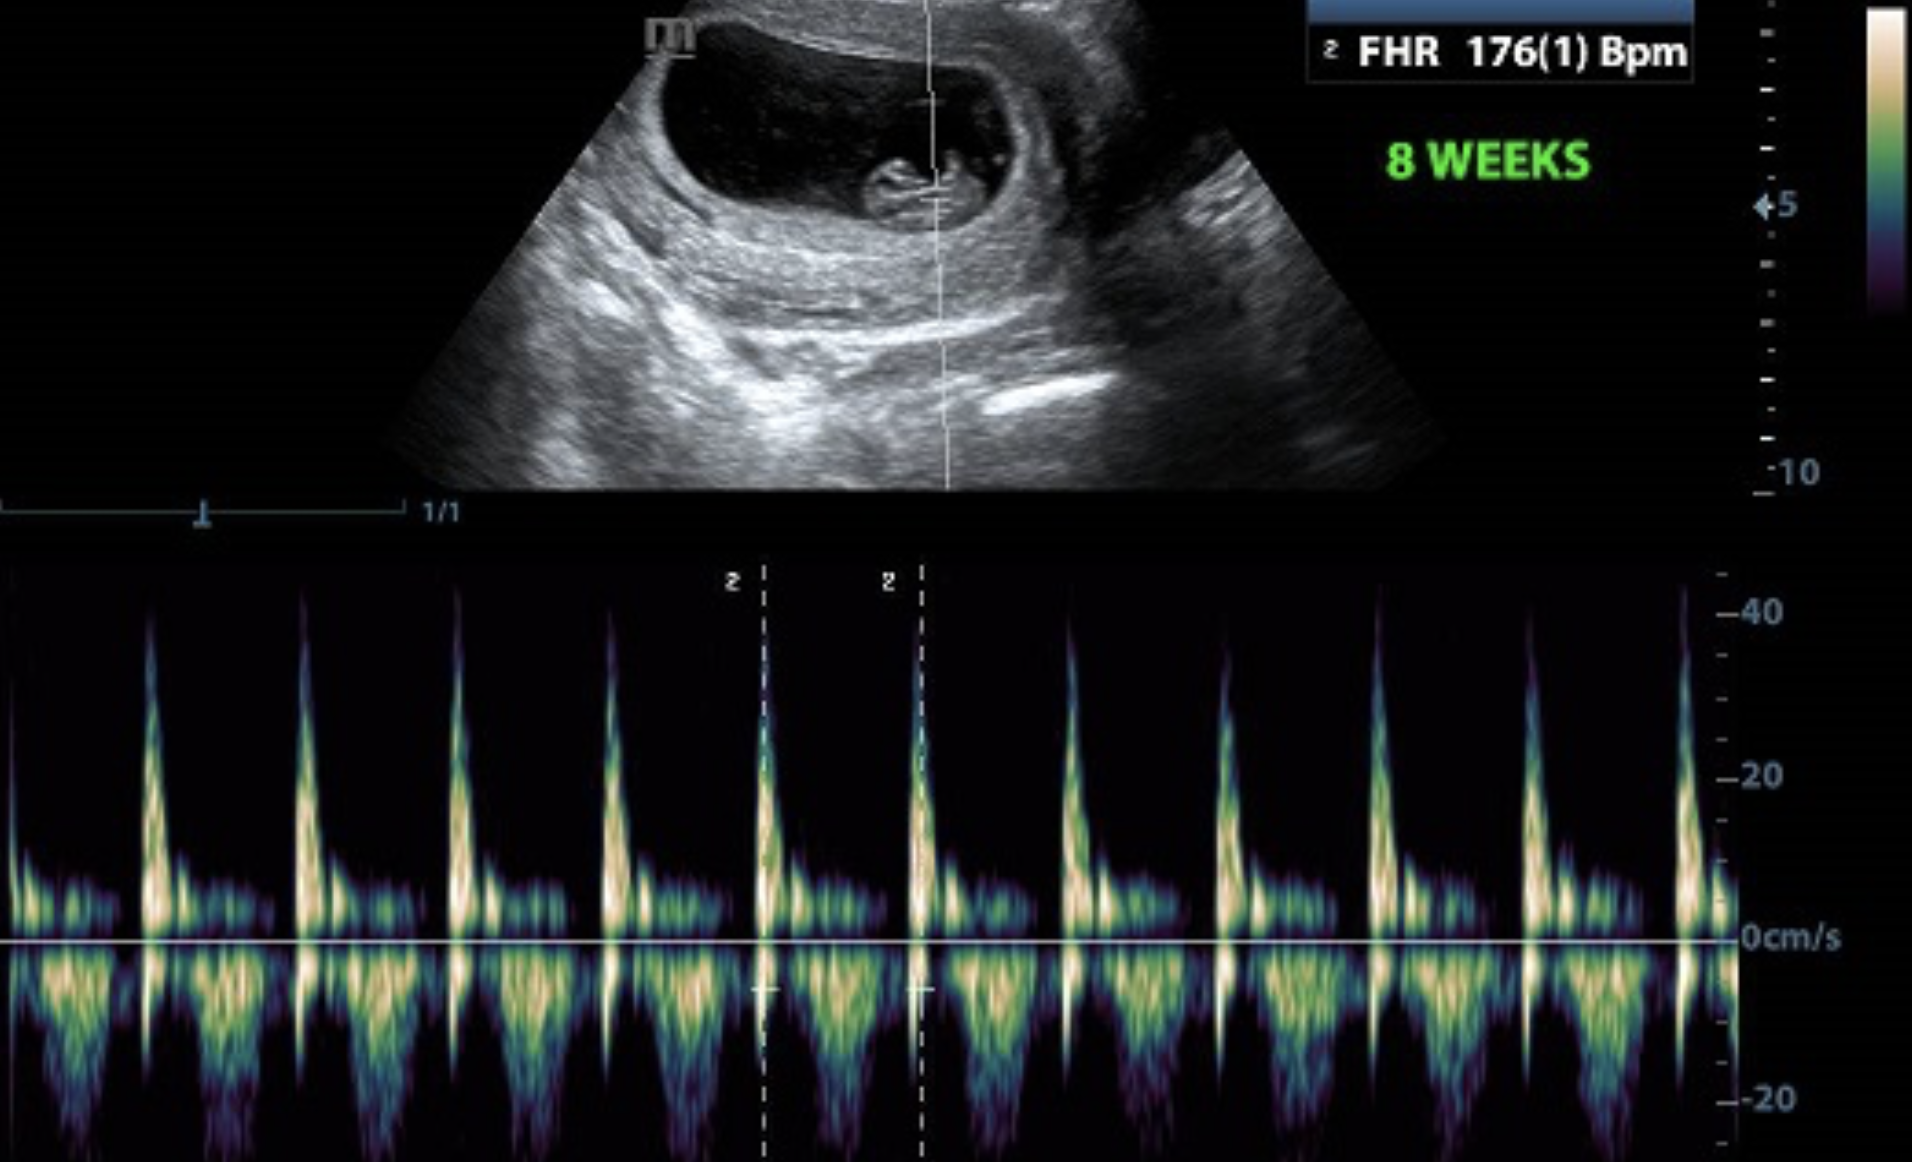

The “Heartbeat Act” classified abortion as a moral a wrong, but by recognizing the criminal act of terminating a fetal life of over six weeks of gestation–as if witnessing the mandated observation of a heartbeat qualified as a crime, and considering abortion a crime that opens all who “aid and abet” its practice, if a physician has already detected the heartbeat, as already mandated by Texas law. Linking the threshold at which a woman can receive a legal abortion to the time of the first ultrasound–about eight weeks, even if the heartbeat of the fetal pole can be sensed earlier, as early as five and a half weeks, this is the first time that the heartbeat can be mapped onto a visible fetal form by trans-vaginal ultrasound, and the heart beating at a rate of ninety to one hundred and ten beats a minute. Governor Greg Abbott of Texas, acting as if he was the state sheriff, proclaimed with the satisfaction of the convert that “every unborn child with a heartbeat will be protected” from September 1, 2021, asserting “no freedom is more precious than life itself,” as he relished reduced freedom of access to abortions if they clashed, as was apparent, from the protection due to the unborn beating heart of the unborn from “the ravages of abortion.” Abbot’s rousing social media post declaring Texas’ protection of fetal rights used the word heartbeat to register of “the steady and repetitive rhythmic contraction” or cardiac activity–

But the “Heartbeat Laws” enacted at some forty East Texas towns, and from Ohio to Kentucky to Texas, seem to take advantage of the gaps between expert medical knowledge and presuppositions of fetal health, able to incentivize the possibility of civil suits against not women seeking abortion, or abortion providers, but anyone assisting in the illegal activity of terminating the alleged “heartbeat” that is posited as an index of vitality. At all of six weeks, a heart has not actually formed in the fetus, but the signals registered on the ultrasound are impressive–and graphically demonstrable–as a life line of sorts that the woman bearing the fetus is forced to face, as if she were suppressing her emotional attachment to the fetus she is carrying, but might reconsider her plans or own health needs before a line registering the presence of some electrical activity approximating a sinus rhythm–or, as the lawyers who parsed the new law put it in tortured prose, “cardiac activity” that involved the “steady and repetitive rhythmic contraction of the fetal heart within the gestational sac”–not an actual heartbeat but a surrogate form of personhood.

While the question of access to abortion threatens to be existential for many women in the United States to a degree that would turn back the clock on what had long been guaranteed to be the accepted “law of the land,” the increased space that was given to legislatures of individual states to determine access to what they have called the termination of pregnancy : the heartbeat has gained currency as the new symbol of the shifting of the grounds of debate, as the heartbeat serves to provide a semantic shift from abortion to “termination,” and the ending of what is now construed as “fetal life,” as the heartbeat first seen in the fetus at about eight weeks has provided the new threshold for allowing abortion in Texas–and perhaps soon in other states–a rhetorical shift in the logic of shifting the threshold from “viability”–the ability of the fetus to live outside of the womb–to the first registration of this totem of life in the womb. Although the fetal heartbeat is able to perceived as rhythmic at just three weeks, when a tiny 40,000 cell embryonic heart works in synchrony with the mother’s heart, as if learning its rhythm, beating the vital rhythm that Goethe elevated to a macrocosmic vibration “an eternal movement of systole and diastole of the heartbeat, the inhalation and exhalation of the world in which we live, act, and exist.” Anti-abortion activists legislated that harmony at a remove from the world, in the womb.

The registration of the heartbeat is of course now captured by sonography, reflecting the emergence of the sonogram as a rite of passage of hospitalized childbirth. The battle in Texas returned to a more recent battlefield than 1973. Local law had tried to recast the “strict scrutiny” of protections on abortion mandated since Roe v Wade from “settled law.” In elevating heartbeats to the standard to “protect the unborn” seem to elevate scientific criteria over legal decisions, but hopes to extricate abortion from constitutional rights in deeply premodern ways. Texas’ Attorney General, Kenneth Paxton, grumbled that after an earlier Supreme Court had acted to overturn restrictions that the Texas Governor in 2013 imposed on access to abortion in the state, introduced in 2013 by then-Governor Rick Perry, that “The court is become a default medical board for the nation, with no deference to state law,” as if Texas legislature were a better tribunal–or as if the hospital could be a tribunal of judging the termination of pregnancy.

The introduction of the mandatory sonogram ten years ago in Texas, intended to force the pregnant mother who has concluded she wants an abortion to listen to the heartbeat of the fetus she seeks to terminate, provided a foundation for the enactment of the “heartbeat” law. But the law makes the mandatory sonogram a compulsory surveillance of her uterus–although if, and only if, the fetus indeed has an irreversible medical condition, the woman carrying it need not hear described the results of what the sonogram revealed. The function of the sonogram was not diagnostic of fetal health, in other words, bu would exist solely to saddle the mother’s conscience, as if she has not taken responsibility for the unborn she carrying, or “to promote informed consent” after listening to the hearbeat registered by a transvaginal probe, used to get the best “look” at the fetus possible.

Although several federal judges have blocked restricting abortion to a time when most women do not register pregnancy, the call to acknowledge the heartbeat a basis for personhood of a fetus promoted by Faith2Action as a compelling basis for generating public support for their bill, using the now universal registration of the sonogram that offers the basis to detect the heartbeat’s detection in hospital clinics, use what seem objective and scientific criteria to advocate prescriptive laws that are far more premodern–and authoritarian–than the constitutional grounds abortion was construed fifty years ago, when Roe v. Wade set criteria of “viability”–the ability of the fetus to sustain vital functions outside the womb–as a commanding parameter of abortion in 1973.

14. While the fiction of the human sentience of a fetal heartbeat is an odd index of life, the associations of the heart with the soul, and human spirit, run deep. the logic of the recent decision to grant the status of the performance or assistance in an abortion after a window of six weeks into term–a window so small only some women may even detect the pregnancy–raises not only epistemic challenges, but elevates the abortion to the status of a citizen’s arrest, a concept akin to vigilantism, but a pillar of Texas’ criminal code that effectively allows the state to step outside federal law. The very fact that Texas courts apply identical rules to arrests by private citizens as to law enforcement officers for reacting to a “breach of the peace” may have planted the seed for pursuing the option of a citizen’s arrest for assisting or performing an abortion shifted the line of debate from Roe v. Wade in 2021, months before the Supreme Court plans to rule on the constitutionality of banning most abortions beyond fifteen weeks, preempting the ruling on a local level, Texas-style, around the index of the fetal heartbeat’s registration in the ultrasound of a developing baby–even if the heartbeat may not emerge in unborn fetus until over six weeks.

The “six week” period before which an abortion can be seen as a “breach of peace” by Texas law is difficult to challenge. But the six week criteria is hardly scientific–if it claims to be grounded in child development and modern medical instrumentation–but in the social presentation of the images of ultrasounds that have become part of the modern rite of a medically supervised childbirth–a “first image” of the unborn. Anatomists from the 1490s studied intensively the formation of the human fetus, studying the forms of the fetus as so difficult to study lest they dissolve they must be observed in cold water, taking care to peel apart the layers of the unformed body–“aborto” is literally unformed or “brought forth prematurely [into the world].”

But the slightly perverse reading of the ultrasound, an image of what appears early identity, present in the electrical charges whose alternation in the heart’s chambers have already begun to allow blood to circulate in its limbs, so it might gain the benefits of nutrition. While this heartbeat is not the reflection of a pulmonary circulation that defines life in the child, or could be cast as the early sign of some readiness to go forth into the world, it seems to cast the fetus as ready to leave the body with autonomy. There is some sense in which the claims of fetal autonomy and the preservation of life is in fact more early modern, or premodern in their scanning for the seats and signs of vitality in the unborn, rather than modern at all, choosing thresholds of the ability to smile (look it up, twelve weeks!) or the first heartbeat (eighteen days), that suggest the pitfalls of defining “viability” as a threshold, but also the cross-fertilization of knowledge for all via Wikipedia-like politicized Wikis, fueling the fervor of injunctions to pray. For all the legal gymnastics of the parsing of abortion by states rights, what passes as scientific insight as to the standards of life far more early modern in their attempt to define a threshold at which life must be respected and celebrated, or demands respect among all citizens to render the assistance with abortion a criminal act and civil crime. The visuals on billboards focussed on the identity of the infant (or Christ child) and the fetus, the infant substituted for the fetus as, in essence, the plaintiff whose ostensible ‘rights’ pro-life anti-abortion groups claim to represent.